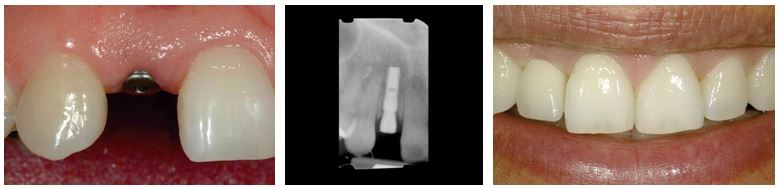

Ersatz eines Zahnes

Nach Verlust eines Zahnes gibt es verschiedene Möglichkeiten, die vorhandene Lücke zu schließen. Eine Variante der oralen Rehabilitation besteht in der Beschleifung der Nachbarzähne und Eingliederung einer Brückenkonstruktion, welche den fehlenden Zahn durch ein Brückenglied ersetzt.

Implantate sind eine Alternative zur Brückenversorgung, da die gesunde Zahnsubstanz der Nachbarzähne erhalten bleibt. Weiterhin spielt die Ästhetik, besonders im Frontzahngebiet, eine große Rolle. Implantate ermöglichen ein perfektes Ausformen der Weichgewebe, so dass sie sich harmonisch in den Zahnbogen eingliedern lassen.